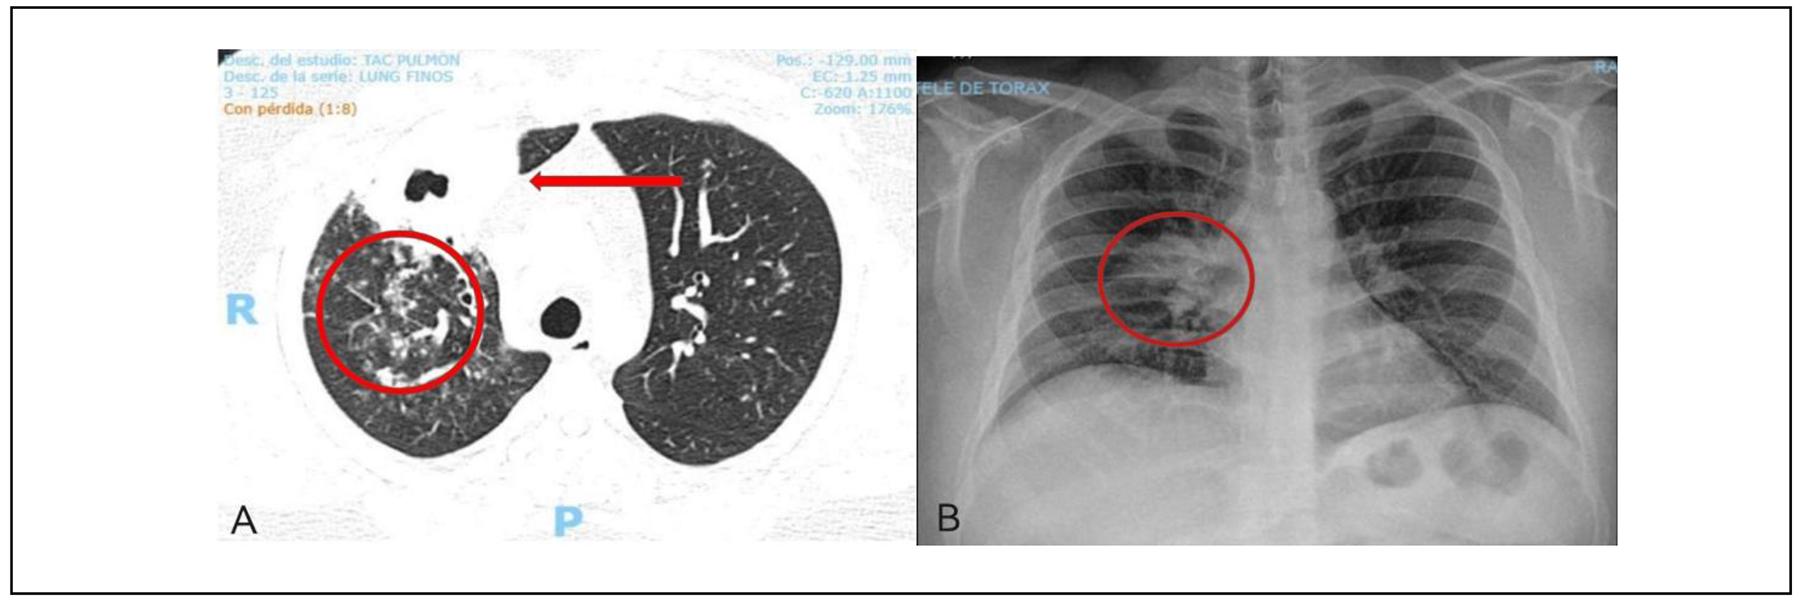

Paciente masculino de 30 años de edad, sin antecedentes personales patológicos, que presenta padecimiento de 6 meses de evolución con tos húmeda en accesos, expectoración hemoptoica y disfonía, se le indicó antibioticoterapia sin mejoría clínica. Se agrega a la sintomatología fiebre de 40°C, y acude con médico neumólogo quien reporta en la exploración física estertores crepitantes anteriores en hemitórax derecho. Los estudios de laboratorio solicitados fueron cultivo bacteriano, cultivo para hongos con desarrollo abundante de Cándida spp, reacción en cadena de la polimerasa (PCR) para Mycobacterium tuberculosis y baciloscopia seriada; en estudios de gabinete se reportó en la radiografía de tórax opacidad parahiliar derecha y en la tomografía axial computarizada (TAC) cavitación en lóbulo superior derecho, llenado perilesional y en lóbulo medio nódulos en árbol de gemación bilateral de predominio derecho (el Cuadro 1 muestra los resultados de laboratorios y la Figura 1 los estudios de gabinete).

Figura 1. A) Tomografía Computarizada de tórax en donde se aprecia la cavitación en el lóbulo superior derecho con espesor de pared de 9 mm, así como medida transversal y de altura de 36 x 60 x 36 mm y media de 8 x 14 mm (flecha roja). Nódulos en árbol de gemación (círculo rojo). B) Radiografía de tórax con opacidad parahiliar derecha de morfología ovalada, con diámetro máximo de 4 cm (Círculo rojo).